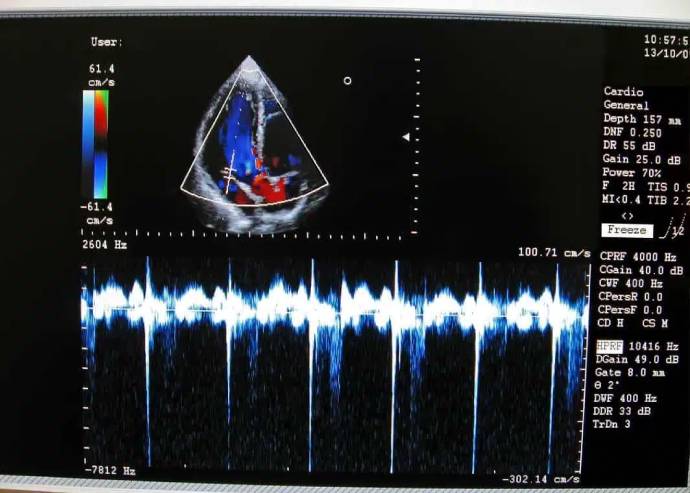

Ultrasonido especializado

- Doppler arterial de miembros pélvicos

- Doppler venoso de miembros pélvicos

- Doppler carotideo y vertebral.